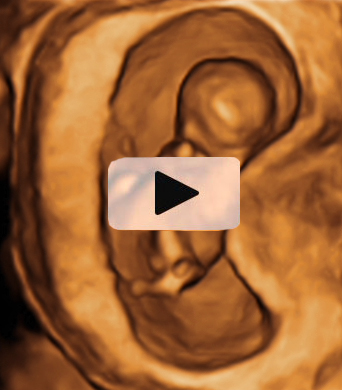

Ecografía 4D semana 12: Bebé con cordón umbilical al cuello

Ecografía en 3D de feto de 13 semanas con el cordón umbilical al cuello

La ecografía en tres dimensiones muestra un feto de 13 semanas de gestación con el cordón umbilical alrededor del cuello. En la imagen rotatoria se puede observar la situación del cordón, que sube por el tórax y que seguramente puede causar complicaciones en el embarazo.